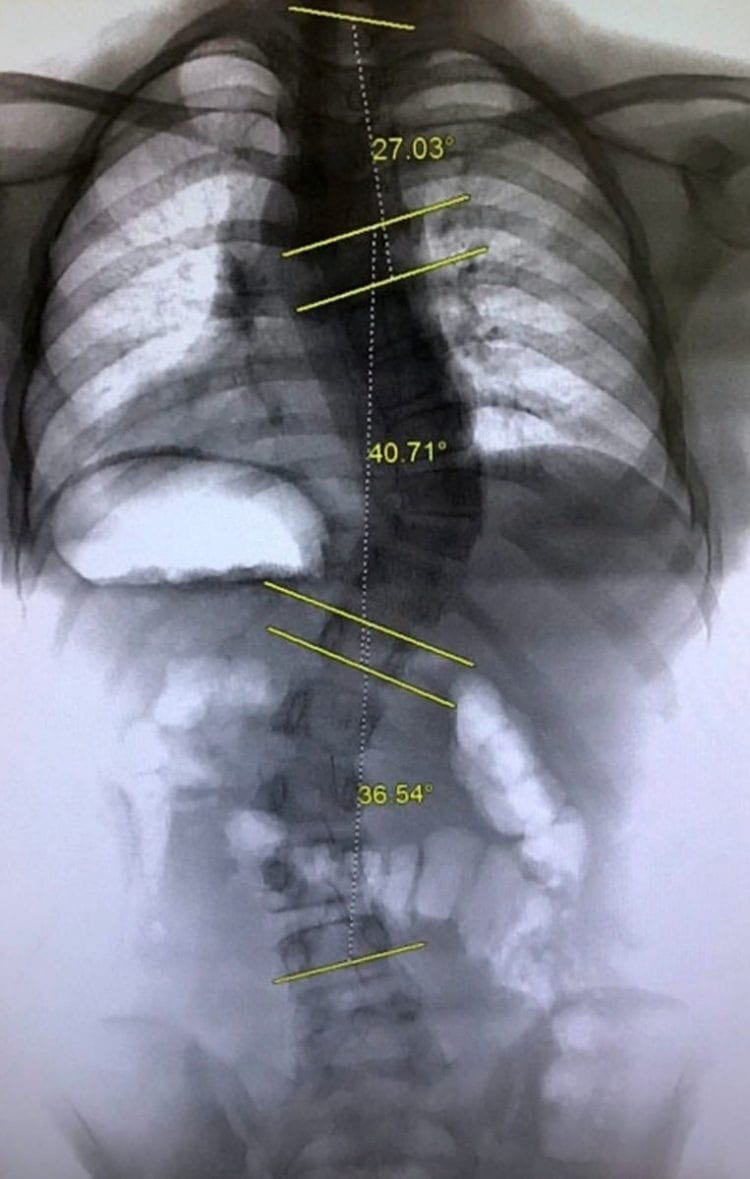

She was diagnosed with severe scoliosis over the summer with three bends in her spine. Her parents only found out when they were out walking the dog and noticed that 11-year-old Izzy’s back was hunched.

The lumbar curve was masking the middle curve so the condition was not spotted earlier. This has bent Izzy’s spine over 40 degrees.